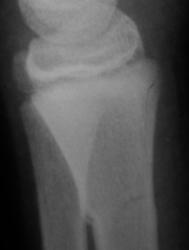

Травма. Пациент направлен хирургом в рентгеновский кабинет для рентгенологического исследования лучезапястного сустава.

Вот она - натуральная  "зеленая ветка"!!!

показательный снимок этого перелома

Кроме основного – "зеленая ветка" – другой недостоверен: может быть артефактом. На боковой рентгенограмме полоса слишком чёткая для нерезкого в целом снимка, похожа на полосы в области запястных костей. Там нет переломов? Подмигивает В прямой проекции обе линии принадлежат поднадкостничному перелому.